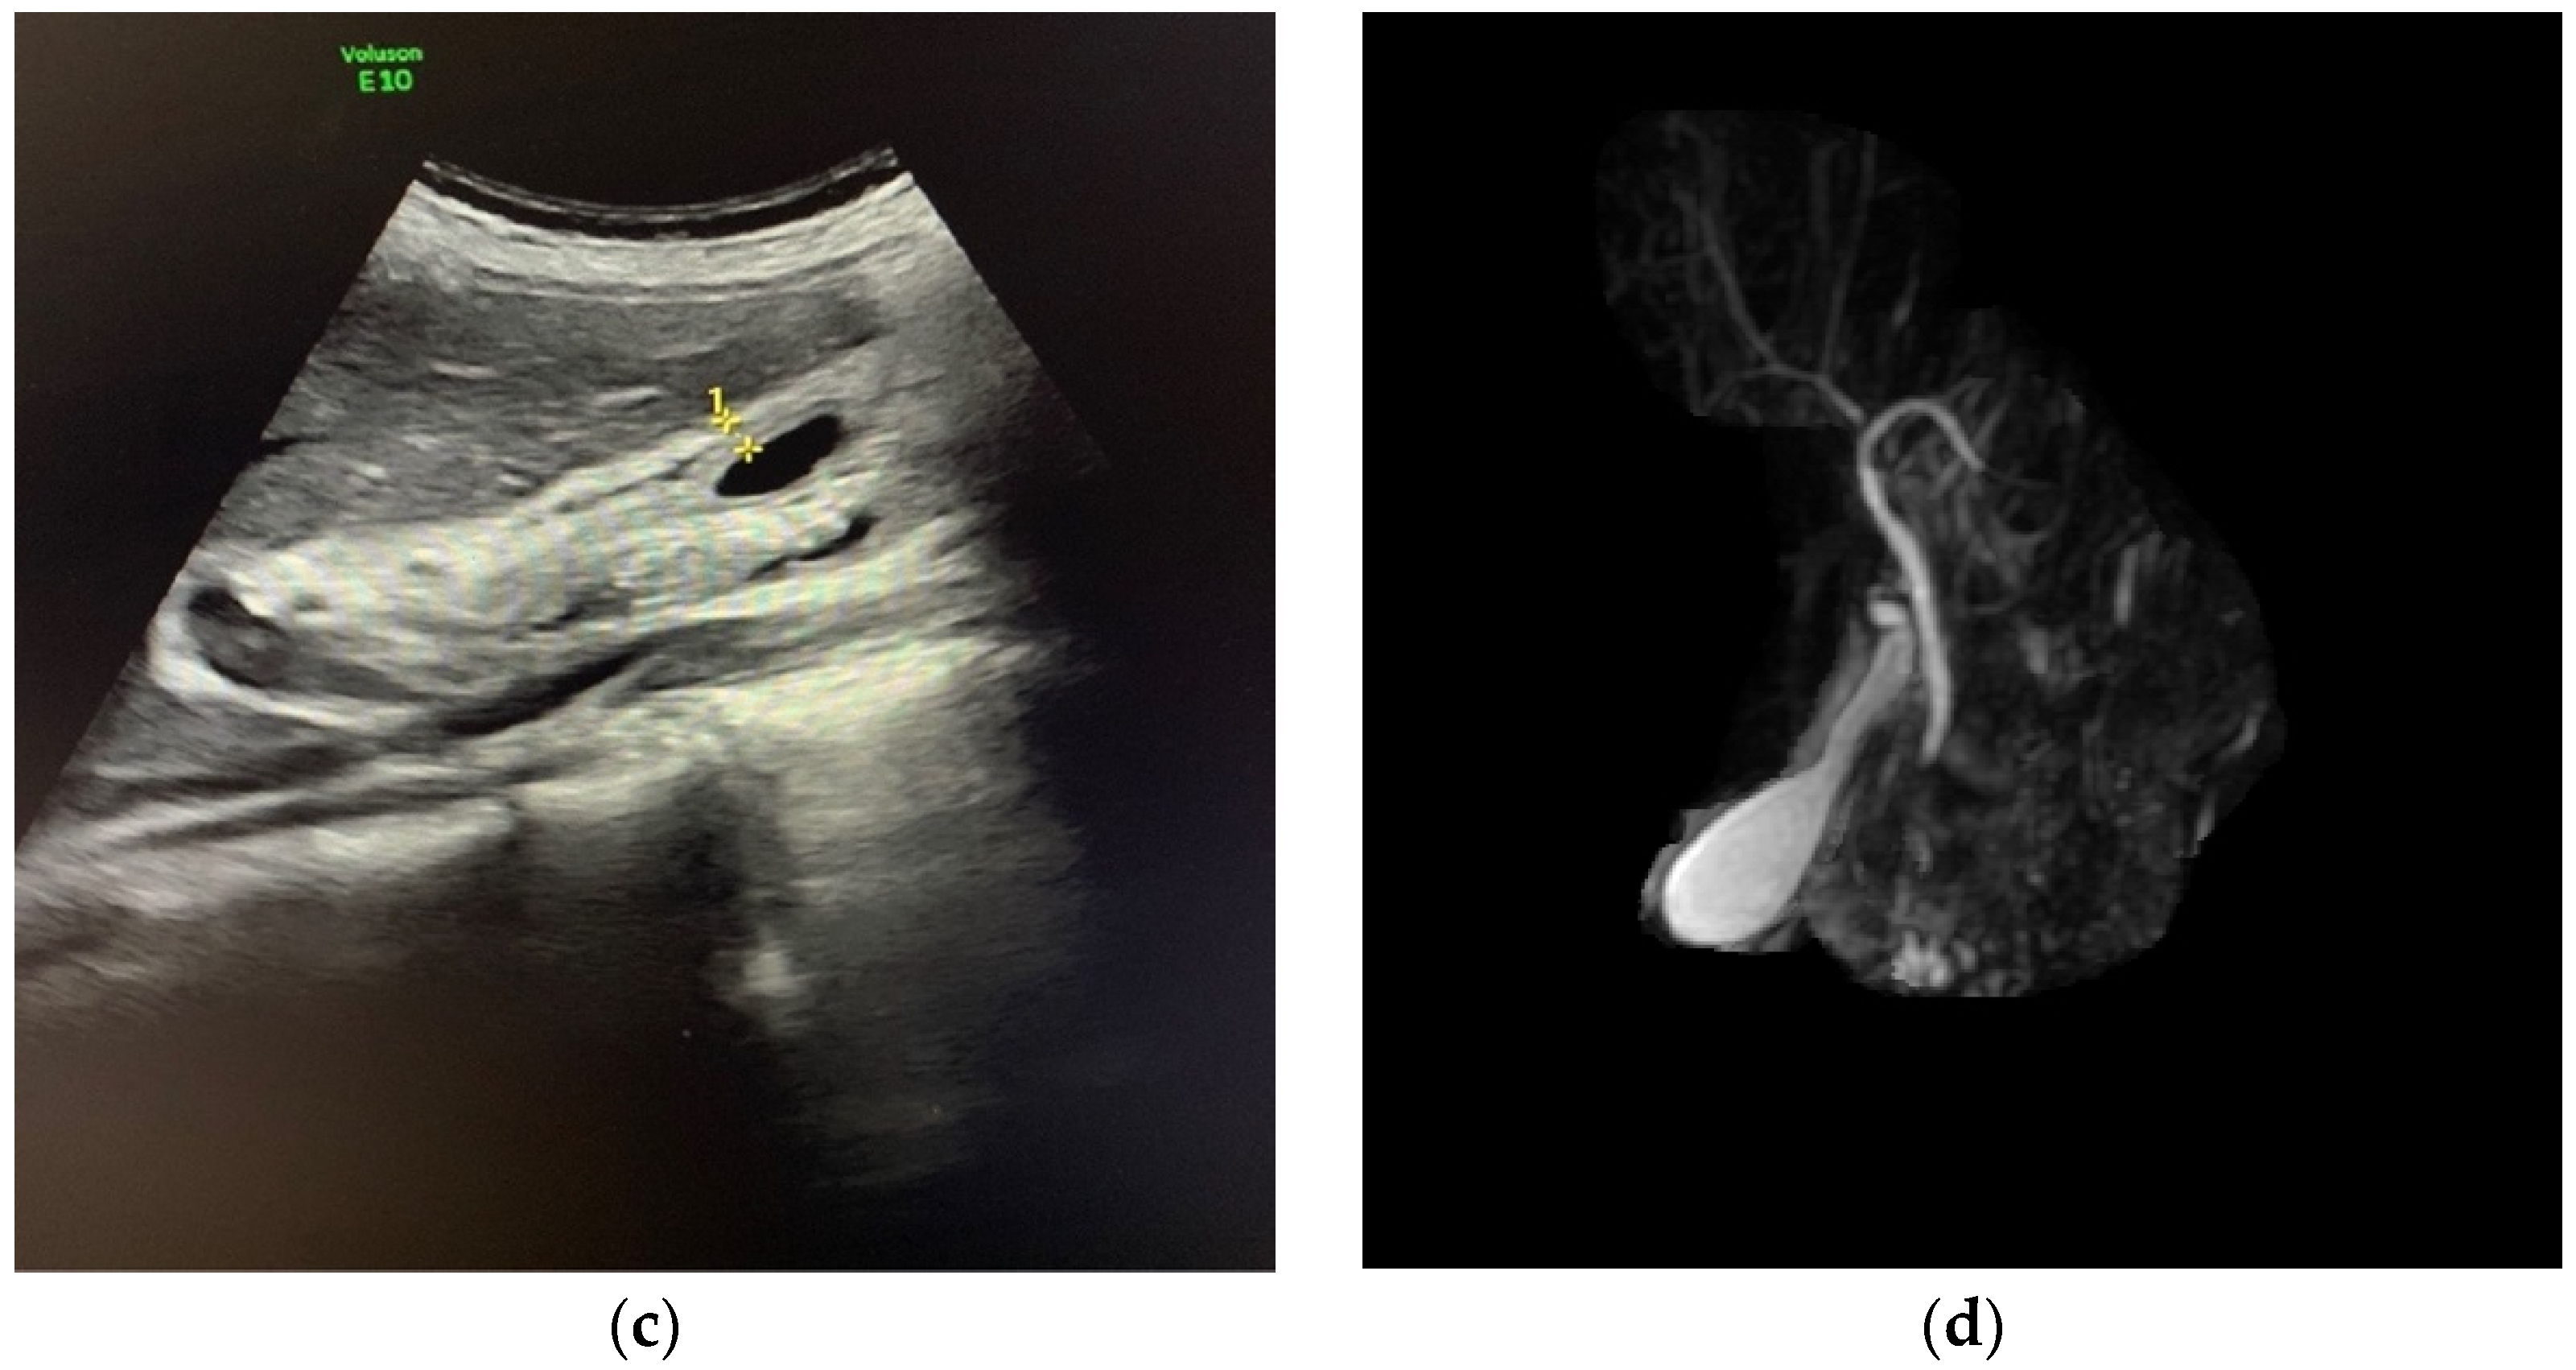

3. Case Report